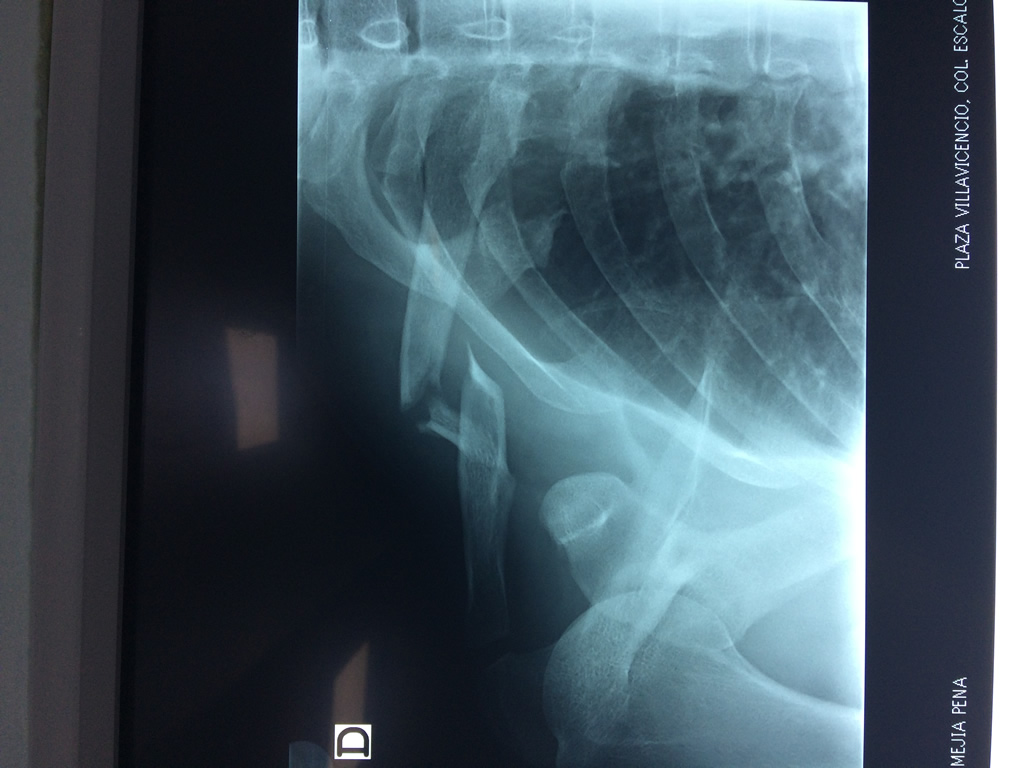

Cirugias en El Salvador - Clavícula

La clavícula es un hueso largo, con forma de "S" itálica, situado en la parte anterosuperior del tórax. Junto con la escápula forman la cintura escapular. Se puede palpar por toda su longitud y se extiende del esternón al acromion de la escápula, siguiendo una dirección oblicua lateral y posterior.

Se considera el único medio de unión entre el miembro superior y el tórax. A pesar de su aspecto, similar al de un hueso largo, posee una estructura semejante a la de un hueso plano, ya que carece de epífisis y de diáfisis, lo que la harían entrar dentro de la clasificación de hueso largo. Carece de un canal medular propiamente dicho.